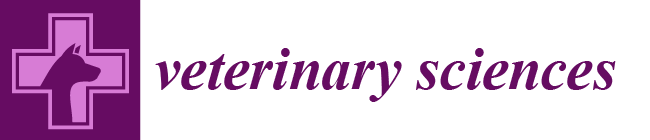

3.3. Ultrasonographic Findings of Subcapsular Thickening

3.4. Ultrasonographic Findings of the Rest of the Kidney

| Distribution | Maximum Thickness (mm) | Echotexture | Echogenicity | Renal Cortical Margin | Renal Capsular Margin | Vascularity | Perirenal Effusion | Architecture | Characteristic Pattern | Corticomedullary Distinction | Renal Pelvis Diameter (mm) | Mineralization | Cystic Lesion | Nodule | |||||

| 1 | 10 year-old, MN, DSH | left | focal | 3.5 | homo | hypo | irregular | irregular | no | no | normal | ill-defined | 1.3 | no | no | yes | Metastatic Carcinoma and Suspected Metastatic Carcinoma (sample obtained from either right or left kidney) | Pulmonary Carcinoma (lung, muscle) | |

| right | focal | 3.5 | homo | hypo | irregular | irregular | no | no | abnormal | hypoechoic striations within hyperechoic areas | ill-defined | no dilation | no | no | no | ||||

| 2 | 15 year-old, FN, DSH | left | focal | 1 | homo | hypo | smooth | smooth | NA | no | abnormal | ill-defined | no dilation | no | no | no | Suspected Metastatic Carcinoma | Pulmonary Carcinoma (lung, muscle) | |

| 3 | 11 year-old, MN, DSH | right | focal | 2.8 | homo | hypo | irregular | smooth | yes | no | abnormal | ill-defined | no dilation | no | no | yes | Suspected Metastatic Carcinoma | Pulmonary Carcinoma (lung) | |

| 4 | 9 year-old, FN, DSH | left | focal | 4.8 | homo | hypo | irregular | irregular | no | no | abnormal | hypoechoic striations within hyperechoic areas | ill-defined | no dilation | no | no | no | Metastatic Carcinoma | Pulmonary Carcinoma (lung) |

| right | focal | 1.5 | homo | hypo | smooth | smooth | NA | no | abnormal | well-defined | no dilation | no | no | no | Suspected Metastatic Carcinoma | ||||

| 5 | 14 year-old, FN, DSH | left | focal | 1.2 | homo | hypo | smooth | smooth | NA | no | abnormal | hypoechoic striations within hyperechoic areas | ill-defined | no dilation | no | no | no | Metastatic Carcinoma | Pulmonary Carcinoma (lung) |

| 6 | 11 year-old, MN, DSH | left | focal | 3 | homo | hypo | smooth | smooth | NA | yes | normal | ill-defined | no dilation | yes | no | no | Metastatic Carcinoma | Metastatic Carcinoma (lung) | |

| right | circumferential | 13.2 | hetero | hetero | irregular | irregular | yes | yes | abnormal | completely effaced | 1.9 | yes | yes | no | Primary Renal Carcinoma | ||||